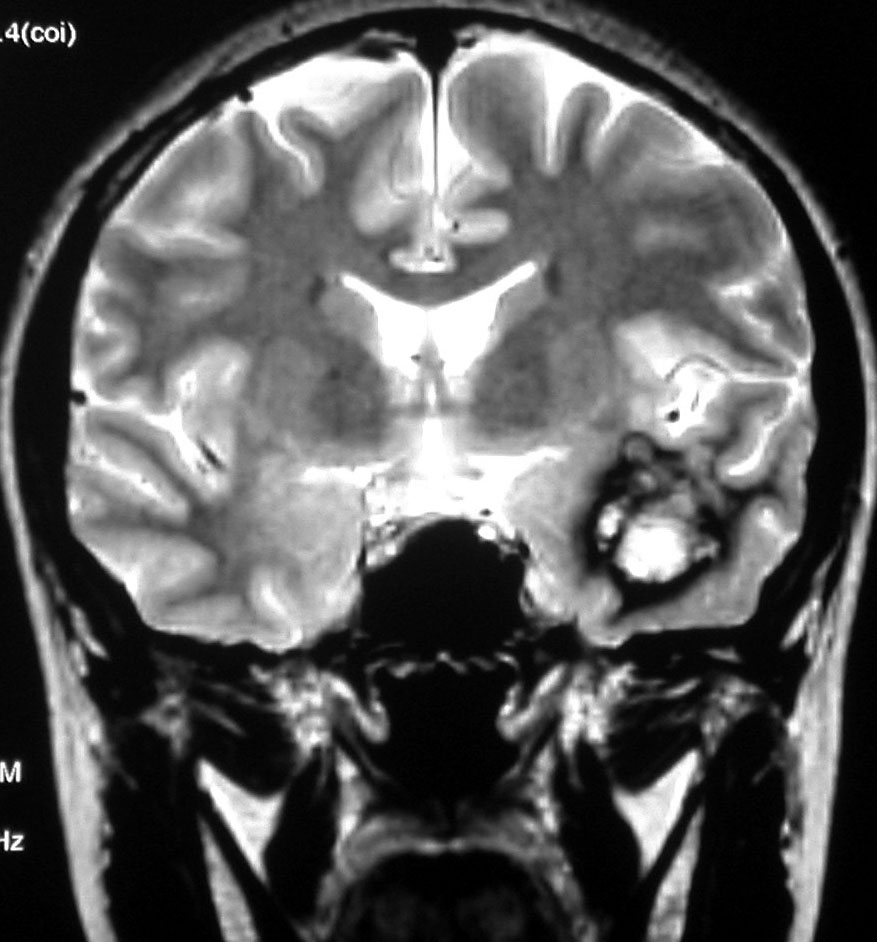

左上のT2*でみられるように多発性海綿状血管腫の成人男性に発生した中脳海綿状血管腫です。複視と歩行失調で発症して,数回の脳幹部出血を繰り返し,水頭症になったために第3脳室開窓術がなされました。それでも出血は止まらず、両側の動眼神経麻痺による両側眼瞼下垂,歩行失調,嚥下障害などさまざまな中脳症状が進行しました。

しかたがないので手術で摘出しました。なんとか眼瞼が持ち上がるようになり歩行も可能で嚥下もできます。幸いだったのは感覚路(脊髄視床路)の障害による体性疼痛が生じなかったことです。

手術は経テント法 OTA という手法でした(クリックと手技が書いてあります)

片方の下丘の損傷だけでは神経脱落症状が出ないので,中脳内部の腫瘍を摘出するには下丘という狭い場所を切開して入りますが,この患者さんは左上丘も出血のために破壊されていて,間口が広かったといえます。でもこの手術は難しすぎるので決して積極的にはしません。